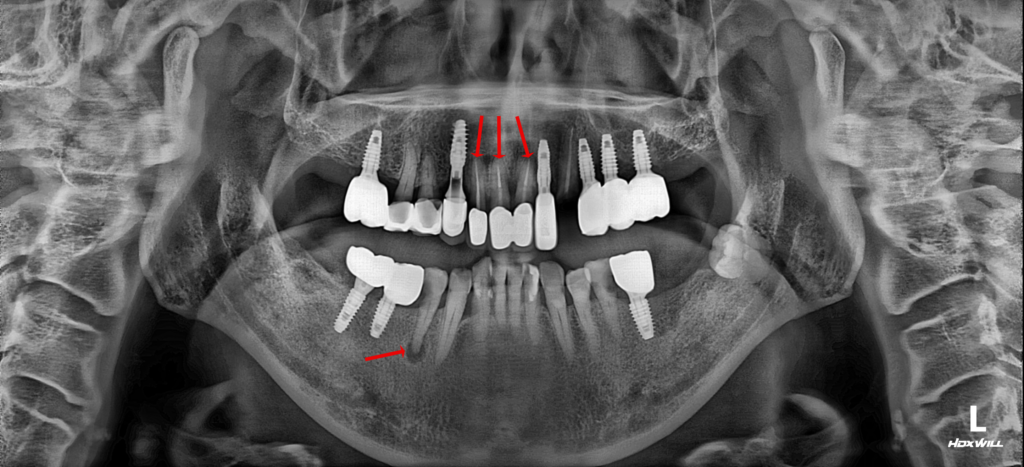

25.10.10

처음 내원하셨을 때의 모습입니다. 화살표로 표시된 치아들이 흔들리고 있었으며 파절치아를 비롯해 장기적인 치료가 필요한 분이셨습니다.

영도치과 서울 화이트S치과는 우선적으로 환자분께서 호소하신 흔들리는 앞니는 살리기 어려워 임플란트 식립을 하고, 오른쪽 아래 작은 어금니는 신경치료와 보철물을 제작하여 살려서 사용하실 수 있도록 계획하였습니다.